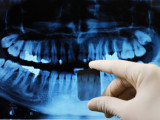

Radiologie

- Les radiographies permettent de visualiser à travers le corps la totalité des dents et leur environnement osseux, ainsi que le crâne et les articulations mandibulaires.

• panoramique ou orthopantomogramme, cette radiographie permet de visualiser la totalité de la bouche, d'une articulation à l'autre.